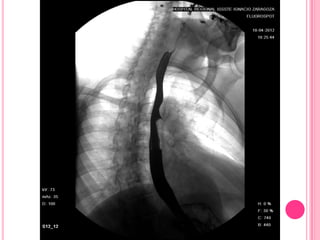

Estudio baritado en paciente con esclerodermia que desarrolló esofagitis

severa por reflujo por la incompetencia del esfínter esofágico inferior